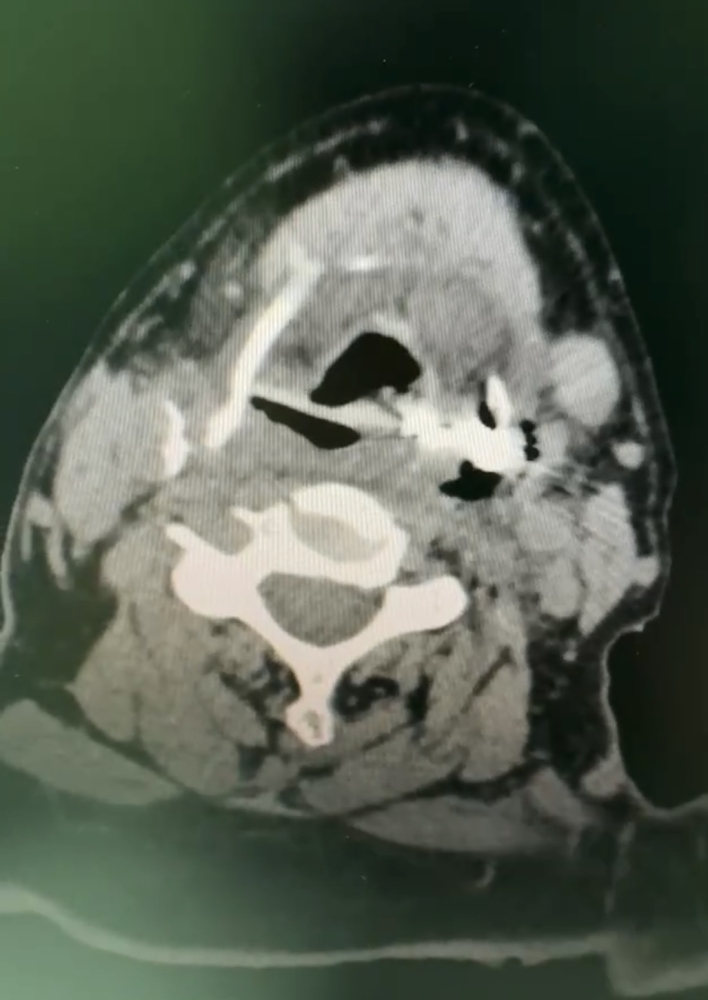

【急诊故事】都是假牙惹的祸 毓璜顶医院10天救治两例误吞整排假牙患者

“医生,我父亲连续两天喉咙疼,而且吃不下东西,呼吸也不太好,到底是怎么回事?”近日,烟台毓璜顶医院耳鼻喉头颈外科主治医师吕亚运接诊了一位高龄患者。“这位83岁的患者曾在外院做了胸部CT和颅 ...